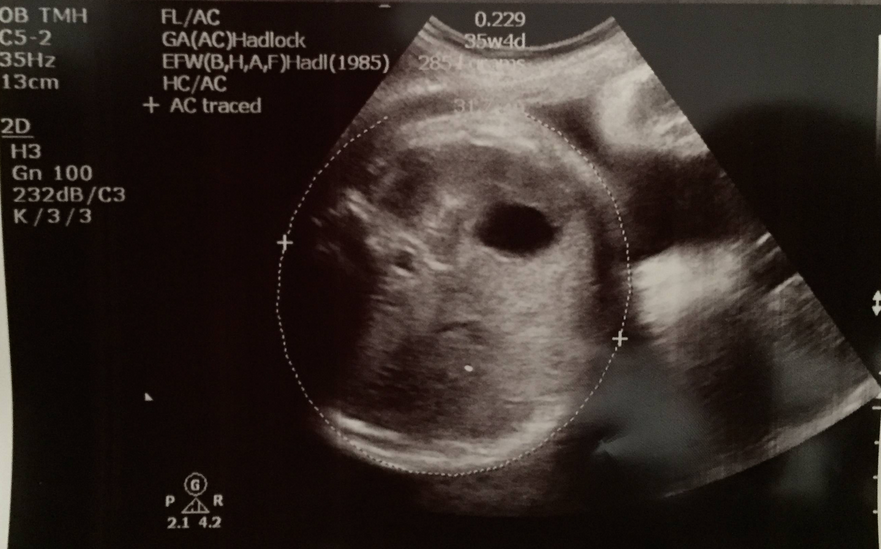

用咗三個parameter嚟計入算式,estimate今日2.97kg,叫做75-90 percentile,比起一個星期前嘅2.7kg重咗200幾gram都好合適丫,而今個星期中做嘅CTG又正常,咁講嘅話我唔重都冇問題丫~我係度咕嚕,我同day都唔高,BB呱又會咁大粒嘅?﹗不過其實我BB時都幾大粒,我38週出世有7磅半,按而家呢個趨勢嚟講BB呱都應該都差不多,day係早產細粒B,都唔知佢如果有機會長到足月係咪都係大隻B?﹗大隻細隻都好,健康就好~